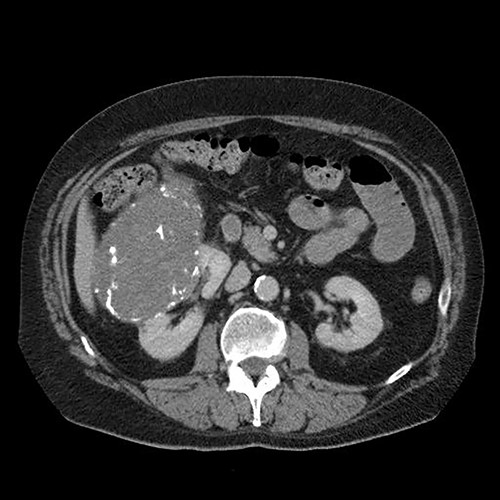

A 65-year-old man with not known malignancy, was admitted to our hospital with symptoms of intermittent bowel obstruction. He had no previous history of abdominal surgery and physical examination revealed abdominal distention, metallic bowel sounds, pallor, and signs of mild dehydration. Furthermore, a fixed subcutaneous lesion was palpated in the right subcostal region. Laboratory tests revealed iron deficiency anaemia. A plain abdominal radiograph in the upright position showed dilated small bowel loops in the upper abdomen. Upper GI endoscopy showed esophagitis and a small hiatal hernia whereas colonoscopy was unremarkable. The abdominal CT scan depicted a large tumour of the right kidney and obstruction of the small intestine at the level of the proximal jejunum (Fig. 1). The persistence of his symptoms led to an exploratory laparotomy and jejuno-jejunal intussusception was found, approximately 50 cm distal to the ligament of Treitz, due to multiple endoluminal neoplastic lesions (Figs 2 and 3). Resection of the affected part of the jejunum and side-to-side anastomosis was performed. In addition, the subcutaneous lesion was removed.

Abdominal computed tomography showing a large tumour of the right kidney and obstruction of the small intestine at the level of the proximal jejunum.